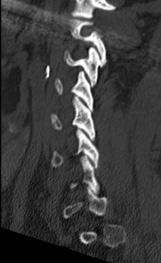

Pre-op CT demonstrates right C5-6 uncovertebral joint osteophyte causing foraminal stenosis but minimal facet arthrosis.